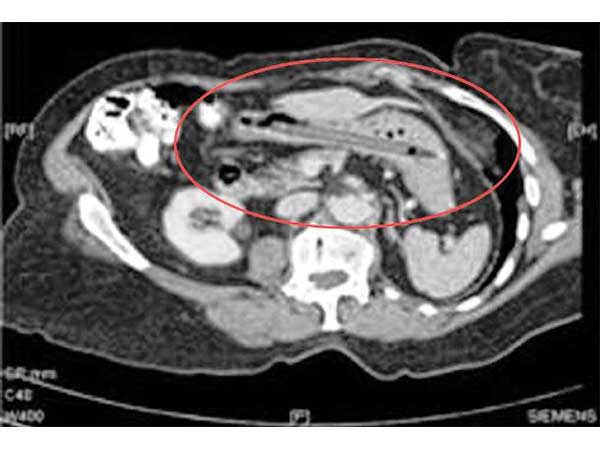

Cutlery

A woman from Netherlands named Margaret Daalman complained about severe stomach ache. When the doctors had a look at the x-ray, it showed that there was an entire set of forks and spoons in her stomach. There were 72 different types of cutleries found in there.